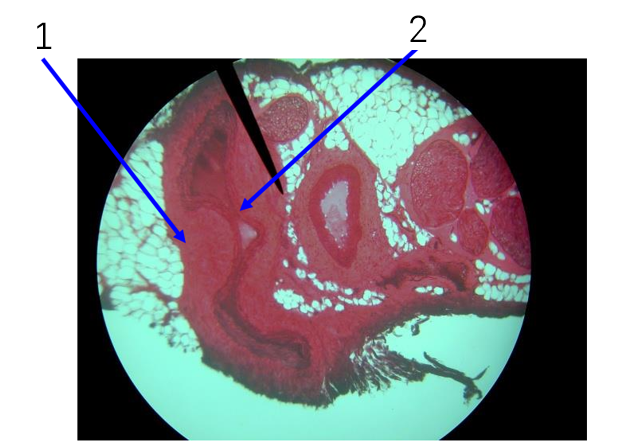

Name number 1

Tunica externa

Name number 2

Tunica media